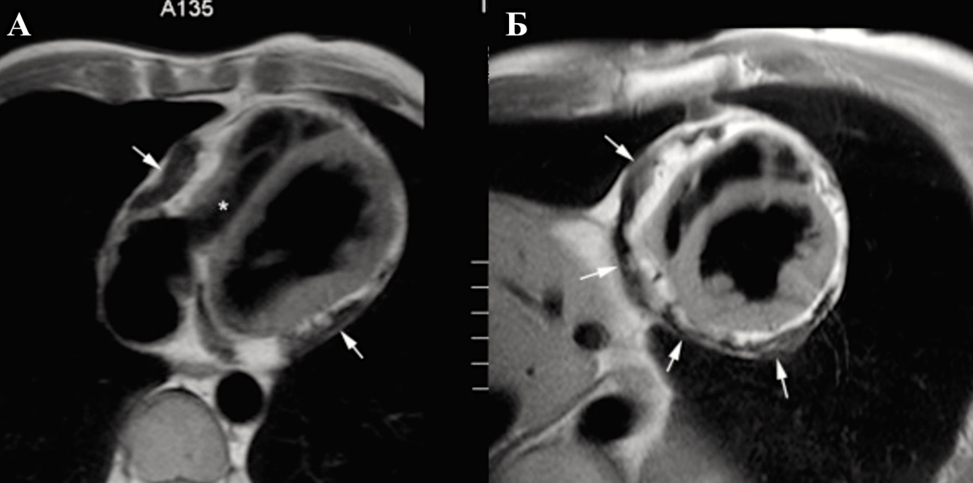

3. Магнитно-резонансная томография

Как и при КТ, МРТ позволяет выполнять прямой анализ количества жидкости в перикарде на основании трехмерной реконструкции ее объема.

МРТ выполняется в режимах «темной» крови и кино-МРТ. Для выявления воспаления листков перикарда и для выявления опухолей перикарда применяется методика МРТ с контрастированием — парамагнитные контрастные средства (гадолинием) в раннюю фазу и в отсроченную (late gadolinium enhancement — LGE).

Следует отметить, что МРТ не позволяет столь же достоверно, как КТ, выявлять и оценивать кальциноз перикарда.

Констриктивный перикардит характеризуется утолщением перикарда, которое больше выражено со стороны правого желудочка и передней атривентрикулярной борозды (Приложение А3, рис. А3-11) [156].

При этом критериями утолщения листков на МРТ считаются [157]:

-

2 мм и менее — без патологии;

2–5 мм и при наличии клинической симптоматики — констриктивный перикардит;

5–6 мм — констриктивный перикардит.

Утолщенный перикард имеет слабую интенсивность сигнала не только на Т1- и Т2-взвешенной спин-эхо МРТ, но и на киноизображениях; в терминальной стадии констриктивного перикардита введения парамагнитных контрастных средств (гадолиний- содержащих) не приводит к увеличению детализации изображения (Приложение А3, рис. А3-12) [158].

Косвенными признаками констриктивного перикардита будут: расширение предсердий, дилатация полых и печеночных вен, асцит и плеврит.

В случаях констриктивного перикардита выявляются значительное утолщение перикарда, между листками которого обнаруживаются спайки c очагами казеозного перерождения и превращения в рубцовую ткань. Также возможно обнаружение обызвествления околосердечной сумки.